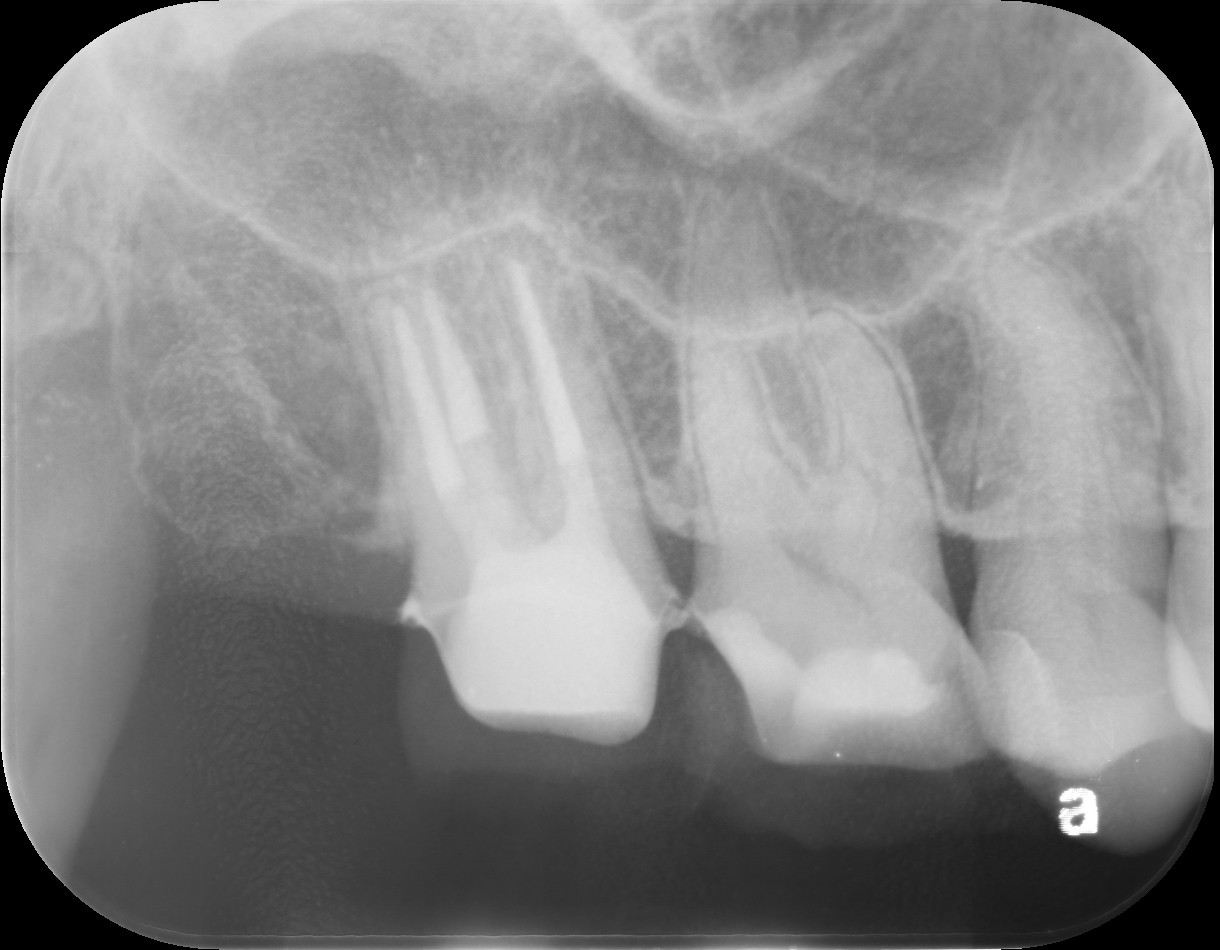

患者は右上臼歯部の歯肉腫脹および清掃困難を主訴として来院した。口腔内診査の結果、右上第二大臼歯遠心部に歯肉の肥厚およびポケットの残存が認められた。特に遠心部では歯肉形態の過剰により清掃性が低下しており、慢性的な炎症が持続している状態であった。

また、右上第一大臼歯および第二大臼歯には既存修復物が認められ、マージン適合および形態の問題からプラークコントロールが困難な状況であった。

歯周基本治療後も右上7遠心部に歯肉の肥厚およびポケット残存が認められたため、ディスタルウェッジ手術を行った。

第二大臼歯遠心部の過剰歯肉を楔状に切除し、歯肉形態を整えることでポケットの減少および清掃性の改善を図った。術後は良好な歯肉形態が獲得され、遠心部のプラークコントロールが容易となった。